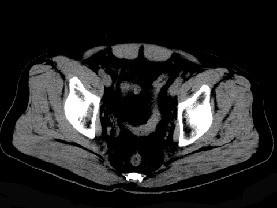

问题 男,56岁,因左髋关节疼痛、无外伤史,体检左髋关节稍肿胀,请结合所提供图像,选择最佳选项 ( )

选项 A、左髋关节滑膜炎 B、左髋关节类风湿关节炎 C、左髋关节退行性改变 D、左髋关节痛风 E、左髋关节滑膜骨软骨瘤病

答案 E